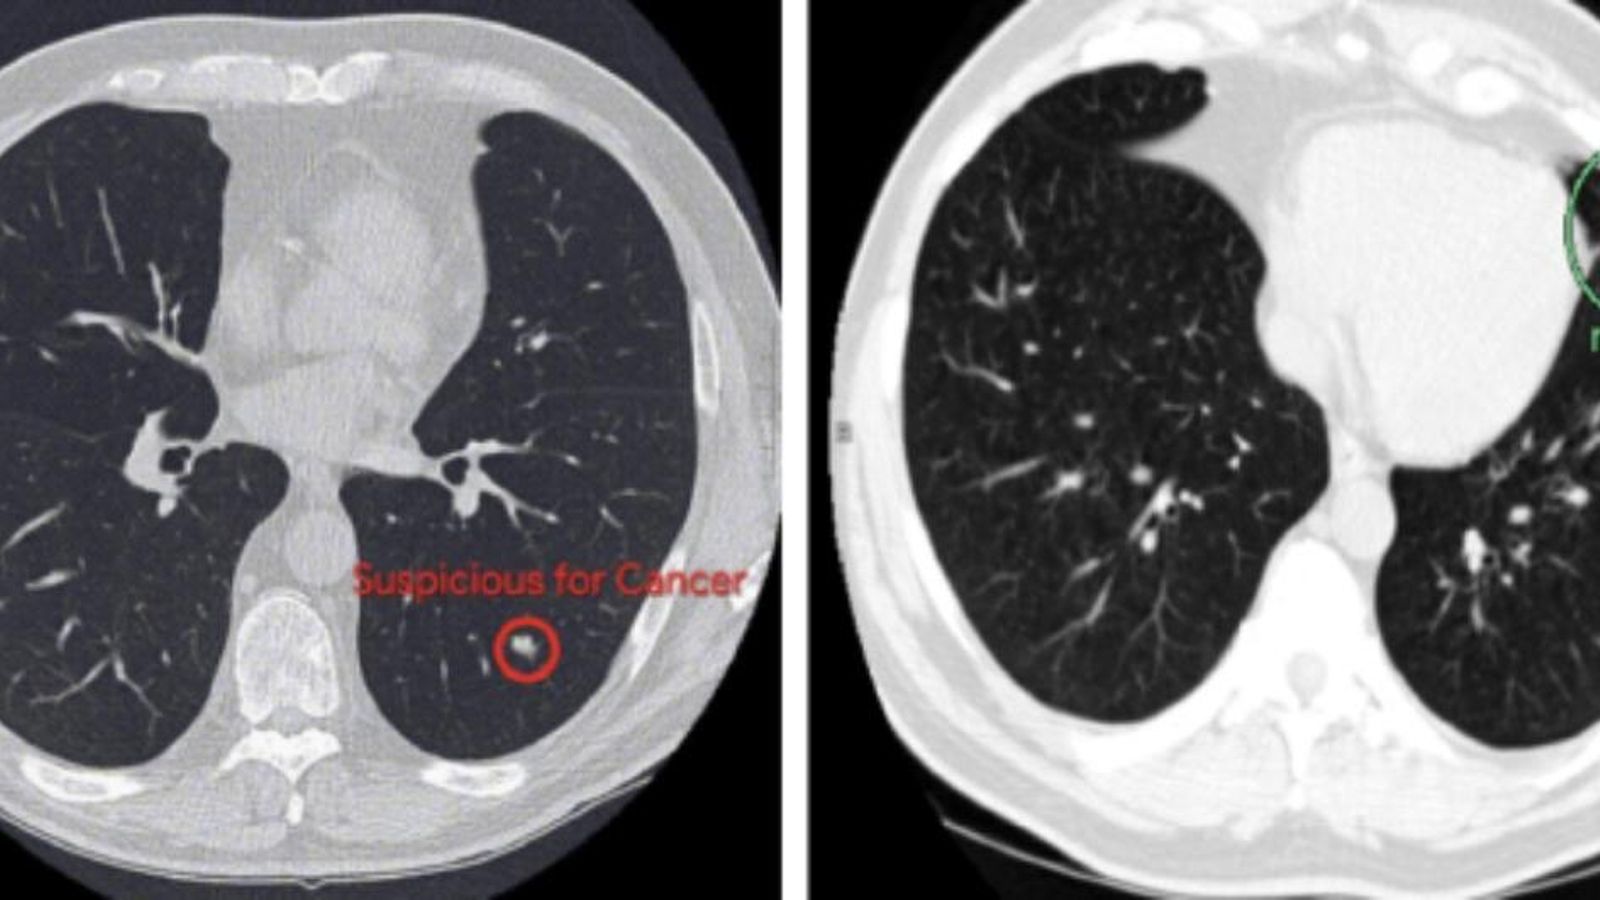

Basant-se en això, l'equip investigador ha desenvolupat un algorisme capaç de detectar nòduls pulmonars malignes, a vegades minúsculs, a partir de resultats d'un TAC -tomografia axial computada- del tòrax, amb una obstinació i precisió igual o millor que el dels radiòlegs.

Per a això, "van entrenar" el sistema amb 42.290 imatges de tomografia computada i van trobar que era capaç de detectar els mòduls amb una precisió del 94% en 6.716 casos de prova.

Mozziyar Etemadi, professor de Medicina i d'Enginyeria en Northwestern i un dels autors de l'article que arreplega la investigació, explica que aquest nou sistema permet analitzar instantànies en 3D. "És capaç d'identificar tant una regió d'interés com si la regió té una alta probabilitat de càncer de pulmó", indica Etemadi